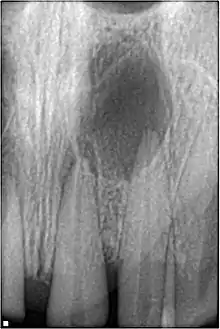

Radiographic signs of periapical inflammation is usually evident in a tooth with necrotic pulp

Pulpal necrosis

Pulp necrosis usually occurs either as ischaemic necrosis (infarction) caused by disruption to the blood supply at the apical foramen or as an infection-related liquefactive necrosis following dental trauma (2). Signs of pulpal necrosis include[40]

• Persistent grey colour to tooth that does not fade

• Radiographic signs of periapical inflammation